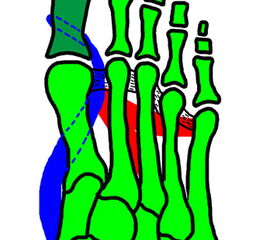

2"> 2" srcset="/assets/images/6/3-j30hz7xkbxcdt1s.jpg 1x, /assets/images/t/3-gct6e1zmng6capw.jpg 1.5x, /assets/images/5/3-qrhzkncpaf3sb3z.jpg 2x" width="270" height="240" loading="lazy">

Abbildung 2

Am häufigsten tritt eine eindimen­sionale Abweichung, in der Regel in Form einer zunehmenden Varusstellung in der Axialebene auf.

Die Beeinträchtigung nimmt mit einer zusätzlichen Fehlstellung in der Sagittalebene zu. Typischerweise besteht dann das Bild einer Hyperextensionsstellung der Großzehe im MTP-Gelenk und eine Flexionsstellung im IP-Gelenk („snake in the grass“ deformity (Wirth, 2002)), eine sogenannte „Malleolus“- Fehlstellung. Bedingt durch die unphysiologische Wirkung der intrinsischen Muskulatur kann eine zusätzliche Rotations-Supinations-Fehlstellung (dreidimensional) entstehen.

Eine weitere Differenzierung ergibt sich aus der Flexibilität bzw. Rigidität der Fehlstellung, welche durch die klinische Untersuchung verifiziert wird. Hierzu ist es erforderlich, den Patienten bei belastetem Fuß zu untersuchen.